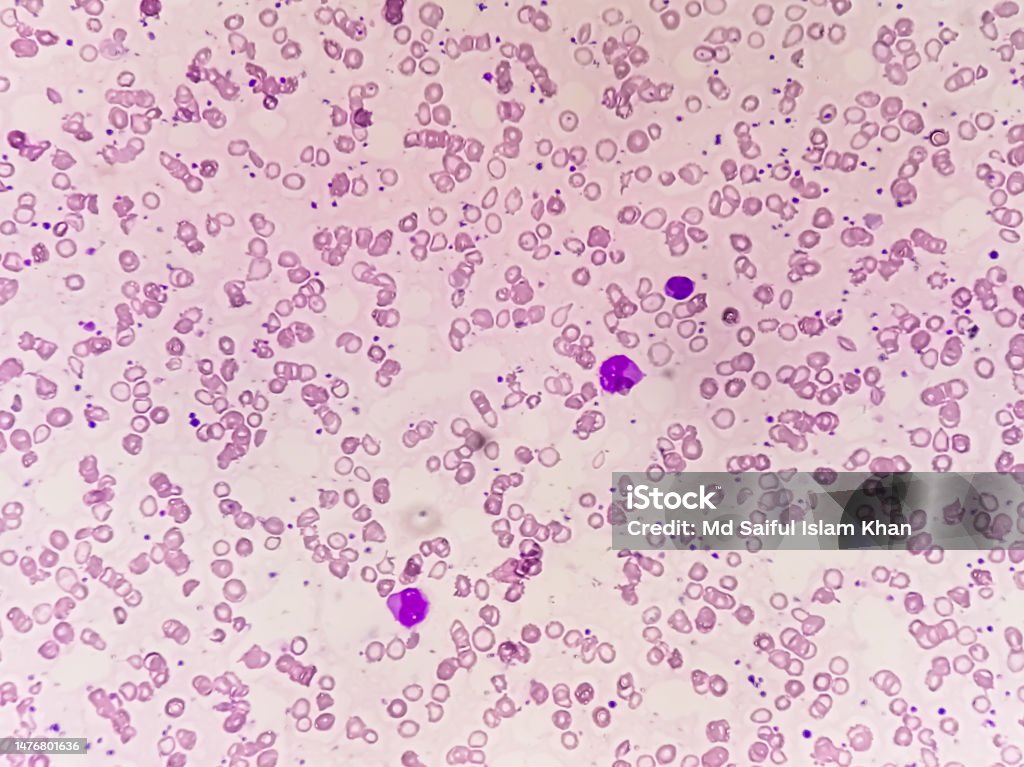

Tear Drop Cells Differential Diagnosis - These tear drop cells are found primarily in diseases with bone marrow fibrosis,. A marked increase of dacrocytes is known as dacrocytosis.

These tear drop cells are found primarily in diseases with bone marrow fibrosis,. A marked increase of dacrocytes is known as dacrocytosis.

A marked increase of dacrocytes is known as dacrocytosis. These tear drop cells are found primarily in diseases with bone marrow fibrosis,.

These tear drop cells are found primarily in diseases with bone marrow fibrosis,. A marked increase of dacrocytes is known as dacrocytosis.

Tear drop cells (Dacrocytes) 1

A marked increase of dacrocytes is known as dacrocytosis. These tear drop cells are found primarily in diseases with bone marrow fibrosis,.

A marked increase of dacrocytes is known as dacrocytosis. These tear drop cells are found primarily in diseases with bone marrow fibrosis,.

Tear Drop Cells

These tear drop cells are found primarily in diseases with bone marrow fibrosis,. A marked increase of dacrocytes is known as dacrocytosis.

These tear drop cells are found primarily in diseases with bone marrow fibrosis,. A marked increase of dacrocytes is known as dacrocytosis.

Ovalocytes And Tear Drop Cells

These tear drop cells are found primarily in diseases with bone marrow fibrosis,. A marked increase of dacrocytes is known as dacrocytosis.

Blood Film Rbc Hypochromic Anisocytosis With Microcytes Target Cell

A marked increase of dacrocytes is known as dacrocytosis. These tear drop cells are found primarily in diseases with bone marrow fibrosis,.

Tear drop cells (dacryocytes)

These tear drop cells are found primarily in diseases with bone marrow fibrosis,. A marked increase of dacrocytes is known as dacrocytosis.

Tear Drop Cell • The Blood Project

These tear drop cells are found primarily in diseases with bone marrow fibrosis,. A marked increase of dacrocytes is known as dacrocytosis.

A Marked Increase Of Dacrocytes Is Known As Dacrocytosis.

These tear drop cells are found primarily in diseases with bone marrow fibrosis,.